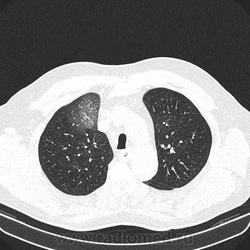

Альвеолярное кровоизлияние.

Полисегментарная пневмония.

оказалось ТЭЛА.

эту пневмонию вылечили, через некоторое время пациент поступил с подобной картиной в другом легком.

потом нашли тромб в артериях н/конечностей.